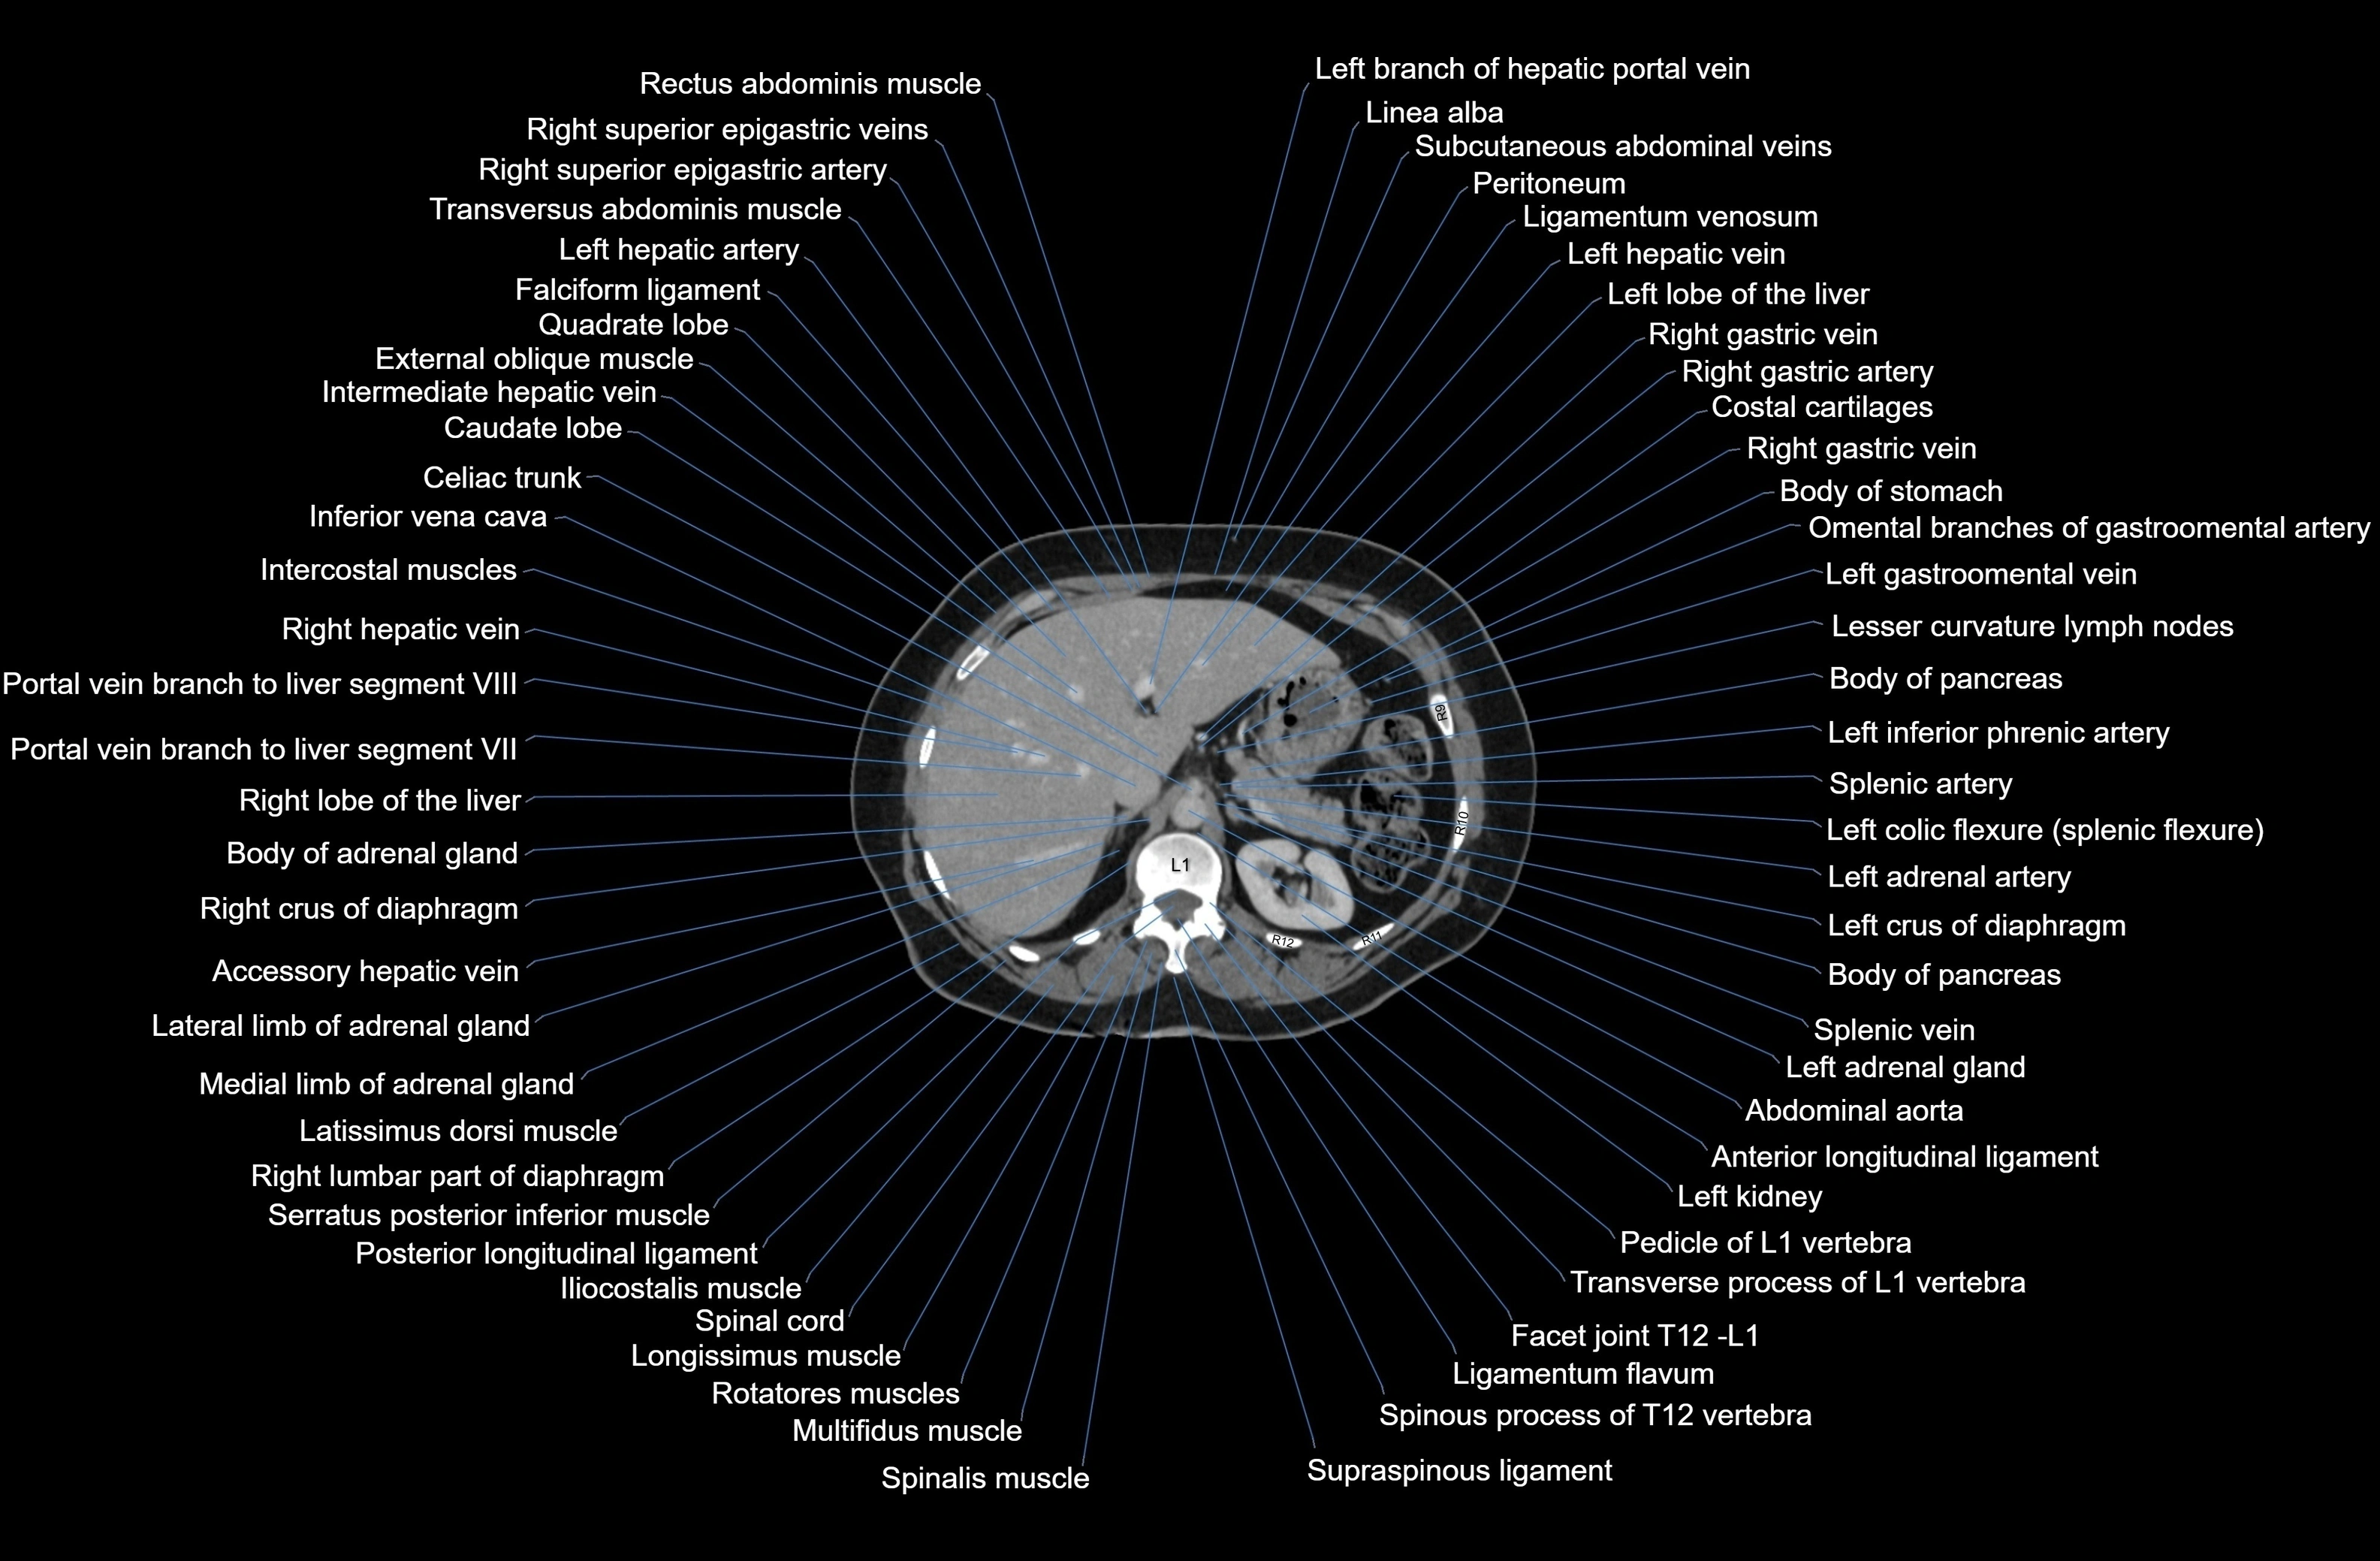

CT images